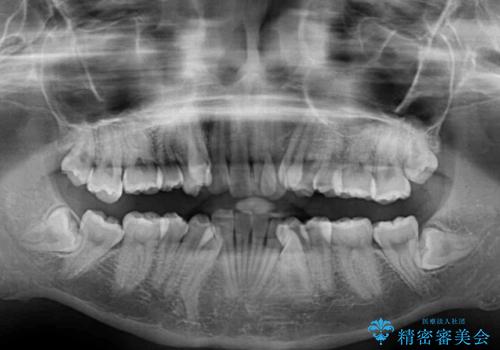

- 上下の八重歯や乱杭歯を気にして来院され患者様です。

スペースを確保するため、上下左右の第一小臼歯を抜歯し、ワイヤー装置に矯正することとしました。